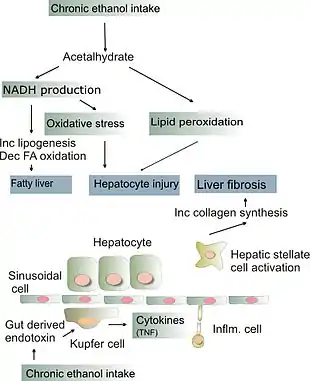

The pathological mechanisms in alcoholic hepatitis are incompletely understood but a combination of direct hepatocyte damage by alcohol and its metabolites in addition to increased intestinal permeability are thought to play a role.[7] Heavy alcohol consumption increases intestinal permeability by causing direct damage to enterocytes (intestinal absorptive cells) and causing disruptions of tight junctions that form a barrier between the enterocytes.[7] This leads to increased intestinal permeability which then leads to pathogenic gut bacteria (such as enterococcus faecalis) or immunogenic fungi entering the portal circulation, and travelling to the liver where they cause hepatocyte damage.[7] In the case of enterococcus faecalis, the bacterium can release an exotoxin which is directly damaging to liver cells.[7] Chronic alcohol consumption may alter the gut microbiome and promote the production of these pathogenic bacteria.[7] Many of these pathogenic bacteria also contain Pathogen Associated Molecular Patterns (PAMPs), extracellular motifs that are recognized by the immune system as foreign material, which may lead to an exaggerated inflammatory response in the liver which further leads to hepatocyte damage.[7]

Alcohol is also directly damaging to liver cells. Alcohol is metabolized to acetaldehyde in the liver via the enzymes CYP2E1 and aldehyde dehydrogenase.[7] Acetaldehyde forms reactive oxygen species in the liver as well as acting as a DNA adduct (binding to DNA) leading to direct hepatocyte damage.[7] This manifests as lipid peroxidation, mitochondrial damage, and glutathione (an endogenous antioxidant) depletion.[7] Damaged hepatocytes release Danger associated molecular patterns (DAMPs) which are molecules that lead to further activation of the immune system's inflammatory response and further hepatocyte damage.[7]

The chronic inflammation seen in alcoholic hepatitis leads to a distinctive fibrotic response, with fibrogenic cell type activation. This occurs via an increased extracellular matrix deposition around hepatocytes and sinusoidal cells which causes a peri-cellular fibrosis known as "chickenwire fibrosis".[7] This peri-cellular chickenwire fibrosis leads to portal hypertension or an elevated blood pressure in the portal veins that drain blood from the intestines to the liver.[7] This causes many of the sequelae of chronic liver disease including esophageal varices (with associated variceal bleeding), ascites and splenomegaly.